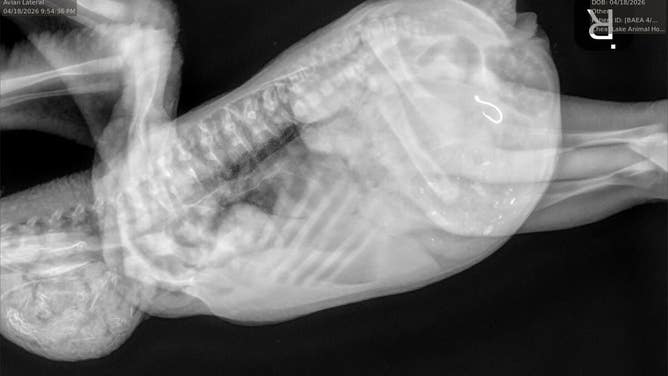

An X-ray of the eaglet, showing the fishhook in its stomach.

(Dr. Jesse Fallon/Avian Conservation Center of Appalachia / FOX Weather)

The eaglet's X-ray, showing the fishhook in its stomach.